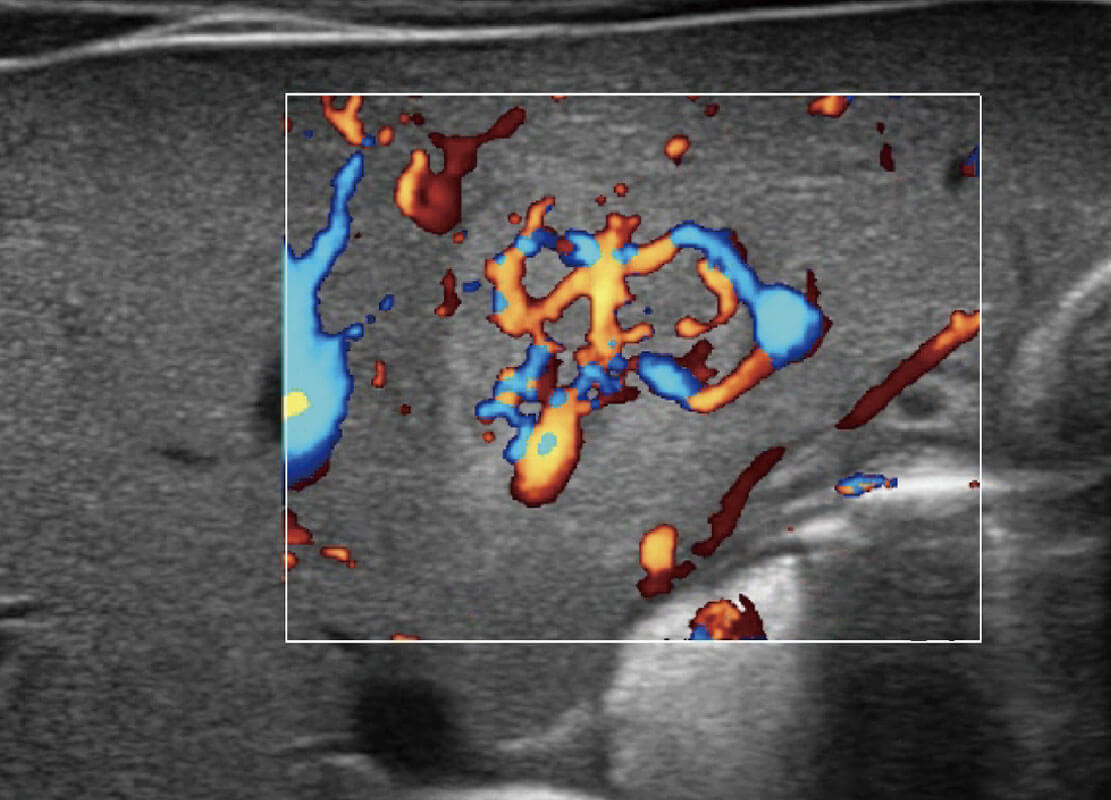

P60优异的图像质量搭载专科探头,在妇科基础疾病的诊断、卵泡生长的监测、输卵管通畅情况的判别等方面为您提供生殖应用方案。

腔内妇科-卵巢

腔内三维-宫内节育器

乳腺癌显微血流